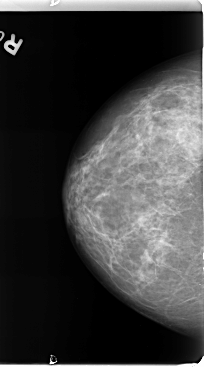

B_3125_1.RIGHT_CC

RIGHT_CC LINES 4768 PIXELS_PER_LINE 2640 BITS_PER_PIXEL 12 RESOLUTION 50 NON_OVERLAY